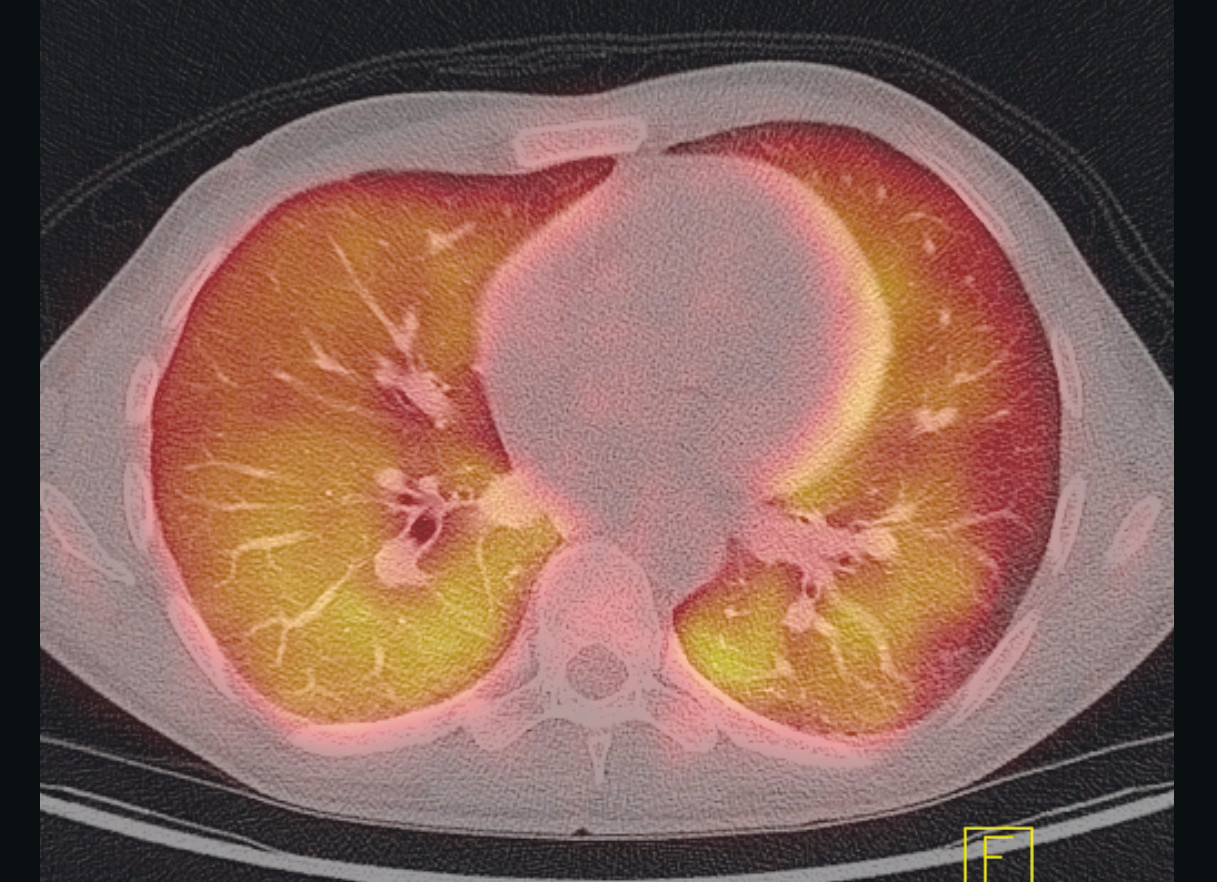

In the days that followed, the patient continued to have episodes of fever and increasing dyspnoea, as well as reduced general condition. PET-CT scan was performed, which showed signs of widespread, diffuse uptake of ¹⁸F-fluorodeoxyglucose (¹⁸F-FDG) in both lungs, as well as reactive spleen and bone marrow (Figure 1).